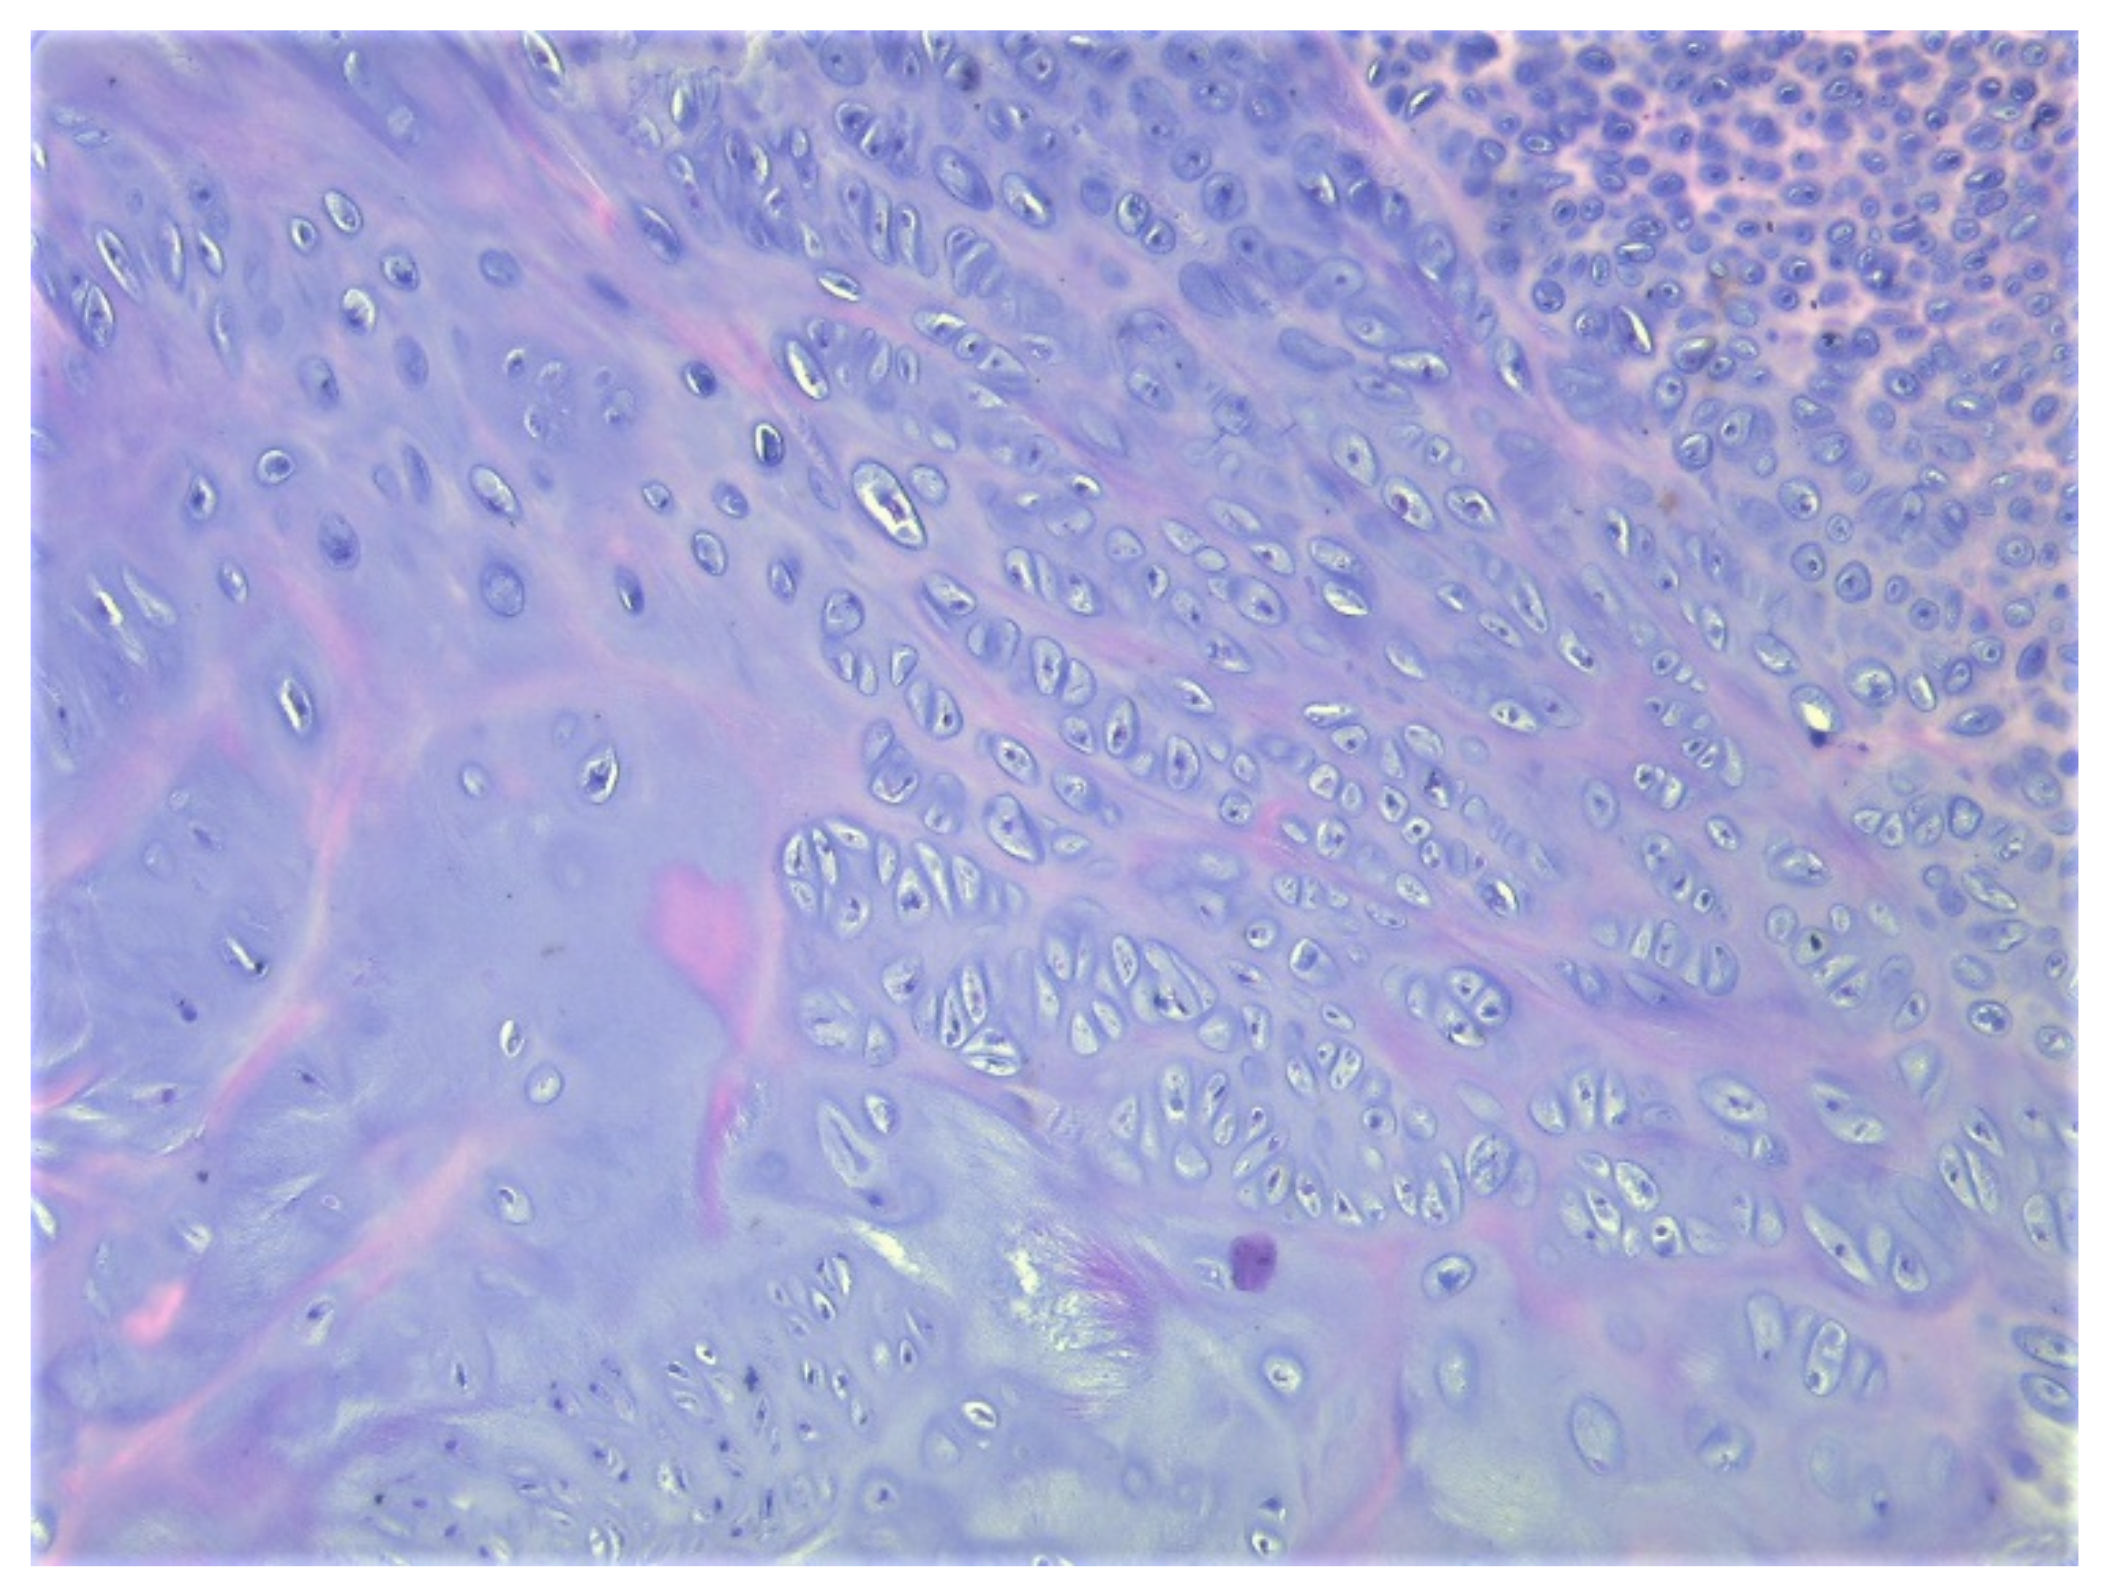

A total of eight tissue fragments, between 0.5 and 3 cm in diameter, were sent for anatomopathological diagnosis. The macroscopic appearance of the tumoral fragments was a nodular polylobate solid mass. On the slide, the top of the tumor was covered by a blue-like cartilaginous cap about 0.1–0.6 cm in width. After decalcification and preparation of formalin-fixed paraffin-embedded tissue blocks the specimen was evaluated. The result indicated tissue fragments made of bone, showing chondroid proliferation on the surface, with minimal cellular atypia, with disorganized distribution and limited columnar pattern at the basal level, slightly increased cellular density, and endochondral ossification with mineralization areas (Figure 9, Figure 10, Figure 11 and Figure 12). Fibroconnective tissue was observed on the surface of chondroid proliferation (perichondrium). The result was indicative for a benign osteochondromatous structure displaying clusters of proliferative chondrocytes in a fibrillary matrix with small ossification centers and small amounts of unabsorbed calcified cartilage. Trabecular bone was covered by an irregular cartilaginous cap.

Figure 10. (A) Disorganized cell clusters with mild cytologic atypia; (B) Areas of cartilaginous tissue undergoing endochondral ossification in to the subjacent trabecular bone, HE, 200×.

Figure 11. Clusters of chondrocytes with uneven cellularity and shape, HE, 200×.